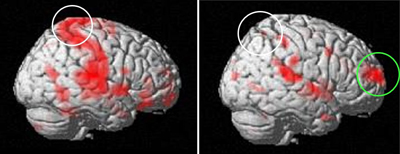

また患者さんが感じる「こわさ」に対して、脳内微小血流変化をとらえ脳賦活部位を特定することで患者さんが自覚する不安感を可視化するfunctional

MRIの研究に取り組んでいます(島根大学医学部医の倫理委員会承認 660号)。この手法は、膝蓋骨脱臼だけでなく膝前十字靱帯損傷の患者さんが感じる「こわさ」を評価することも可能になると考えています。

機能的MRI.左図(健常者)では,task(膝蓋骨を外側へ押す)によって運動認知をつかさどる対側の一次体性感覚野が賦活しているが(白丸),右図(患者)では賦活されていない.将来の予測や情動的ストレス予測をつかさどる背外側前頭前野がtaskによって賦活されている(緑丸).

(門脇,内尾ら.別冊整形外科,2012)